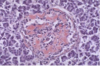

Normal Endocrine Pancreas